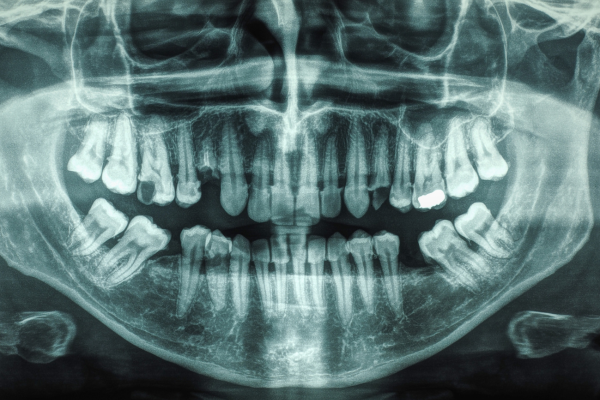

There is only so much we can see without X-rays!

Yes, they are! Dental X-rays often provide information essential for detection, diagnosis, and treatment of conditions that can threaten your oral and general health. Many diseases of the teeth and surrounding tissues cannot be seen during a visual exam. If X-rays are not used, small cavities between teeth, abscesses, cysts, tumors, and other diseases may be impossible to detect until obvious signs and symptoms have developed and serious damage has been done to your health.

Full-mouth Series – This is a complete set of bitewing and periapical X-rays that show all of the teeth, roots, and related areas of the jaws. The number of pictures taken varies depending on the size and shape of the mouth and teeth.

Panoramic – A panoramic view X-ray shows all the upper and lower teeth, large portions of the jaws and other structures in one large picture. It is often used to find unerupted teeth, cysts, fractures, retained root fragments, and other conditions of the jaw. It does not generally show enough detail to be useful for detection of decay and bone loss from periodontal disease.